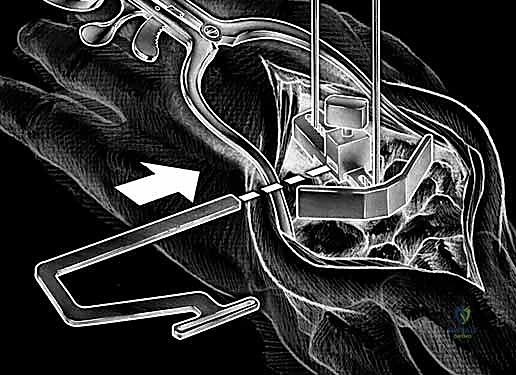

Carpal preparation requires exacting precision. Using the Maestro system as the archetype, the carpal resection guide is positioned to allow resection of 2 to 3 mm of the capitate head. It is provisionally held in position with two 0.062-inch Kirschner wires. The first wire is placed into the capitate neck and the second into the metaphysis of the third metacarpal, ensuring that the guide is perfectly parallel to the third metacarpal axis. With proper placement, the ulnar guide wing will lie close to the triquetrum–hamate articulation, and the radial wing will bisect the scaphoid at its distal third.

With the wrist held in neutral, the radius is scored through the cutting slot in the guide to provide a reference for the distal radial resection. The thumbscrew on the carpal resection guide is loosened to allow insertion of the radial resection guide boom. Following radial resection, the scaphoid, capitate head, hamate edge, and triquetrum are resected at a precise 90-degree angle to the axis of the forearm jig. The trial carpal plate is provisionally determined by the curvature and width of the remaining proximal carpal surface; it must lie flush with the hamate and proximal capitate surfaces. Unlike older designs, it is not always necessary to attempt fusion of the distal pole of the scaphoid to the surrounding carpus. The Maestro Wrist has a provision to replace the entire scaphoid using a carpal plate incorporating a modular radial augment, of which three separate sizes are available.